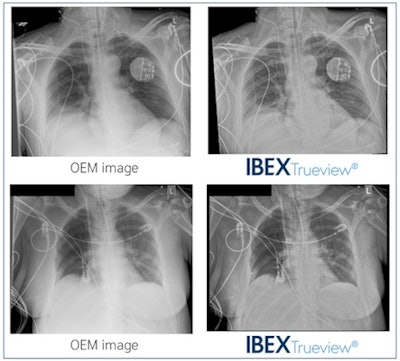

Ibex Trueview is AI software designed to accurately correct for scatter, delivering grid-like diagnostic images with enhanced visibility of tubes and lines in the same contrast stretch, without using a grid, the company said.

In the study, a total of 30 chest x-ray exams were processed using Trueview and compared with standard OEM images by two radiologists and four ICU doctors. Reviewers were more likely to score Trueview higher than OEM for mediastinal structures, bones, retrocardiac region, tube visibility, and tube safety (p < 0.01), according to the findings.

In addition, clinicians were 3.8 times more likely to agree that safe placement of lines and tubes could be confirmed with Trueview images when compared with OEM images.